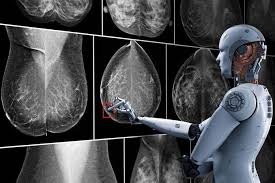

Can Pet Ct Replace Separate Diagnostic Ct For Cancer Imaging Optimizing Ct Protocols For Imaging Cancers Of The Chest And Abdomen Journal Of Nuclear Medicine from jnm.snmjournals.org If you have a pet scan: Bone scans, positron emission tomography (pet), and computed tomography (ct) all continue to be employed alone or in combination for the detection of breast cancers suspected to have spread. Doctors use this type of mammogram in women with breast cancer, but with. Computed tomography (ct or cat) scan. Each has its own strengths. The ct can detect some masses that would then need further evaluation. An mri scan of the breast may be. This lung cancer awareness month learn how future processing is able to detect lung cancer from ct scans with the help of ai.